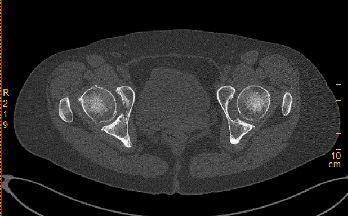

患者,女性,59岁。因“跛行30余年,加重并右髋部疼痛2年”来诊。体格检查:双下肢不等长,右侧髋关节深压痛,双侧髋关节活动受限,右侧显著;右髋关节活动度:屈80°,伸-10°;内收10°,外展20°;内旋:10°,外旋10°;双下肢无明显短缩。患者以右侧髋部疼痛、活动受限为主,左侧无明显疼痛感,给予行右侧全髋关节置换术治疗。

术前X线及髋关节CT图像显示,双侧髋臼明显发育不良,髋臼变浅,右侧髋臼骨质密度不均匀,双侧髋臼对股骨头的包容不足。